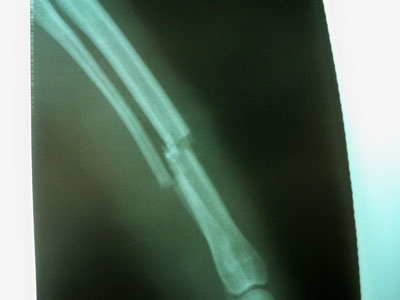

Ημίαιμο καφέ σκυλάκι μεσαίου μεγέθους 3-4 ετών με ιστορικό ατυχήματος στις 30/01/10.Προσκομίσθηκε στο ιατρείο και διαπιστώθηκε κάταγμα στο δεξί πρόσθιο άκρο.Το κάταγμα ήταν τέλειο και εγκάρσιο στο κάτω /3 της διάφυσης της δεξιάς κερκίδας και ωλένης.